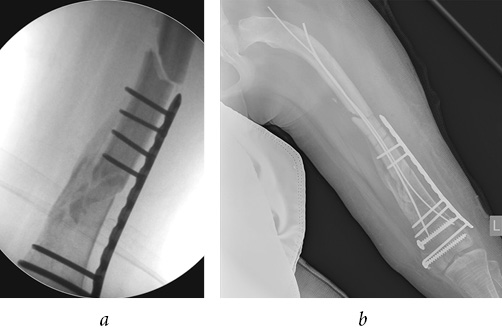

According to the radiographs performed in a primary care facility (of poor quality, in one projection), a closed, comminuted intra-articular fracture of the distal metaepiphysis of left femur (Salter-Harris IV) was diagnosed with a transition to the shaft with the displacement of fragments (Fig. 2); in addition, a closed fracture of the right femoral bone in the lower third of the shaft with mild displacement of fragments was observed (Fig. 3). TEN in the intramedullary canal of right femur prevented a severe displacement of the fragments. As a result of the fracture, TEN was deformed.

Fig. 2. Intraoperative radiographs of the left femur: a — frontal view; b — lateral view

Fig. 3. Intraoperative radiographs of the right femur: a — frontal view; b — lateral view

The first stage of the surgery was osteosynthesis of the distal metaepiphysis of left femur by two cannulated cancellous screws of 6.5 mm in diameter with full threading and with washers above and below the growth zone. Next, an attempt at retrograde osteosynthesis of TEN d = 3.0 mm was made from the standard approaches proximal to the growth zone. Due to the extremely low quality of the bone tissue and the comminuted nature of the fracture of metaphyseal zone, the titanium rods broke the cortical layer of the bone at the site of their insertion or perforated the opposite cortical layer (Fig. 4). It was decided to perform antegrade insertion of internal fixation devices. The rod was inserted through the lateral cortical layer of the upper third of femur and brought to the distal metaepiphysis, and then fixed in place with screws. Due to the small size of the distal metaepiphysis, in order to ensure satisfactory fixation, we perforated the growth zone. The distal end of the rod was placed behind the proximal screw and in front of the distal screw before being fixed in the subchondral zone of bone. Osteosynthesis with a second rod was not possible due to the narrow intramedullary canal. Enlarging the canal by drilling was technically impossible without additional surgical access, which would have significantly increased blood loss, volume, and time of surgery (Fig. 5 a).

Fig. 4. Intraoperative radiograph, TEN perforation of the opposite cortical bone layer

Fig. 5. Postoperative radiographs: a — left femur, frontal view; b — right femur, frontal view

The fracture of the lower third of the shaft of right femur was with insignificant displacement due to the presence of a TEN in the intramedullary canal. The TEN arched, resulting in an angular deformity in the anterior-posterior direction. After performing a closed reposition, it was possible to eliminate the antecurvation of the femur and reduce the rod deformity. The distal end of the TEN was located deep in the cortical layer of the lower third of femoral shaft. We considered it inappropriate to remove it because of the inevitability of additional bone trauma and an increase in the time of the surgery, instead proceeding with the aim of replacing it with a longer TEN, Then, antegrade osteosynthesis with TEN d = 3.0 mm was performed through the medial part of the femur. The intramedullary canal in the middle third of the shaft was very narrow, so it was not possible to insert the rod to the proximal part. The rod was fixed in the shaft of the bone in hard contact with the second rod (Fig. 5 b). Upon completion of the surgical stage, both limbs were immobilized with posterior polymeric splints from the gluteal region to the lower third of the tibia for a period of 4 weeks.